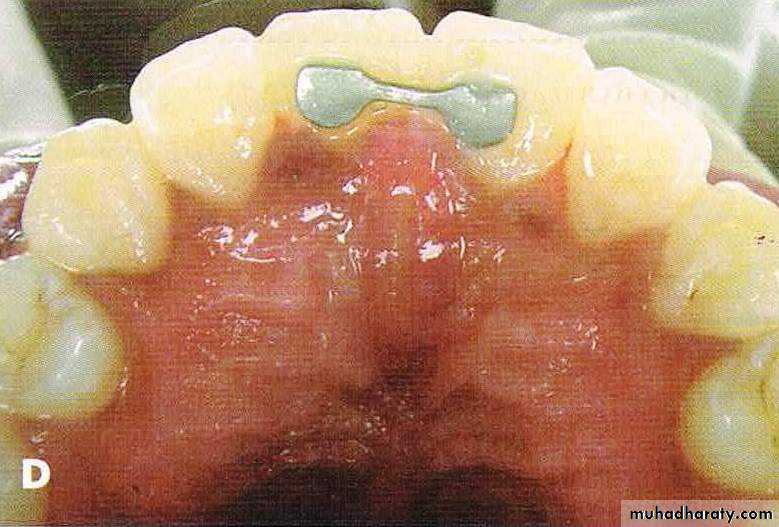

A, Bilateral constricted maxilla with upper midline shift; B, type 1 RME appliance in mouth;

C, end of expansion; D, correction of upper midline shift at end of retention period.